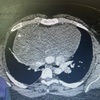

Homem, 60anos, dor torácica e abdominal de forte intensidade há 2 horas.

Dissecção de aorta abdominal, com artéria renal direita oriunda da luz falsa.